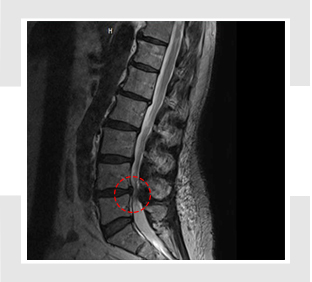

- MRI 검사: 척추관의 좁아짐, 디스크 돌출, 신경 압박 정도를 정확히 볼 수 있습니다. (가장 정확한 검사)